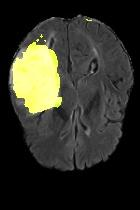

Current unsupervised anomaly localization approaches rely on generative models to learn the distribution of normal images, which is later used to identify potential anomalous regions derived from errors on the reconstructed images. However, a main limitation of nearly all prior literature is the need of employing anomalous images to set a class-specific threshold to locate the anomalies. This limits their usability in realistic scenarios, where only normal data is typically accessible. Despite this major drawback, only a handful of works have addressed this limitation, by integrating supervision on attention maps during training. In this work, we propose a novel formulation that does not require accessing images with abnormalities to define the threshold. Furthermore, and in contrast to very recent work, the proposed constraint is formulated in a more principled manner, leveraging well-known knowledge in constrained optimization. In particular, the equality constraint on the attention maps in prior work is replaced by an inequality constraint, which allows more flexibility. In addition, to address the limitations of penalty-based functions we employ an extension of the popular log-barrier methods to handle the constraint. Comprehensive experiments on the popular BRATS'19 dataset demonstrate that the proposed approach substantially outperforms relevant literature, establishing new state-of-the-art results for unsupervised lesion segmentation.